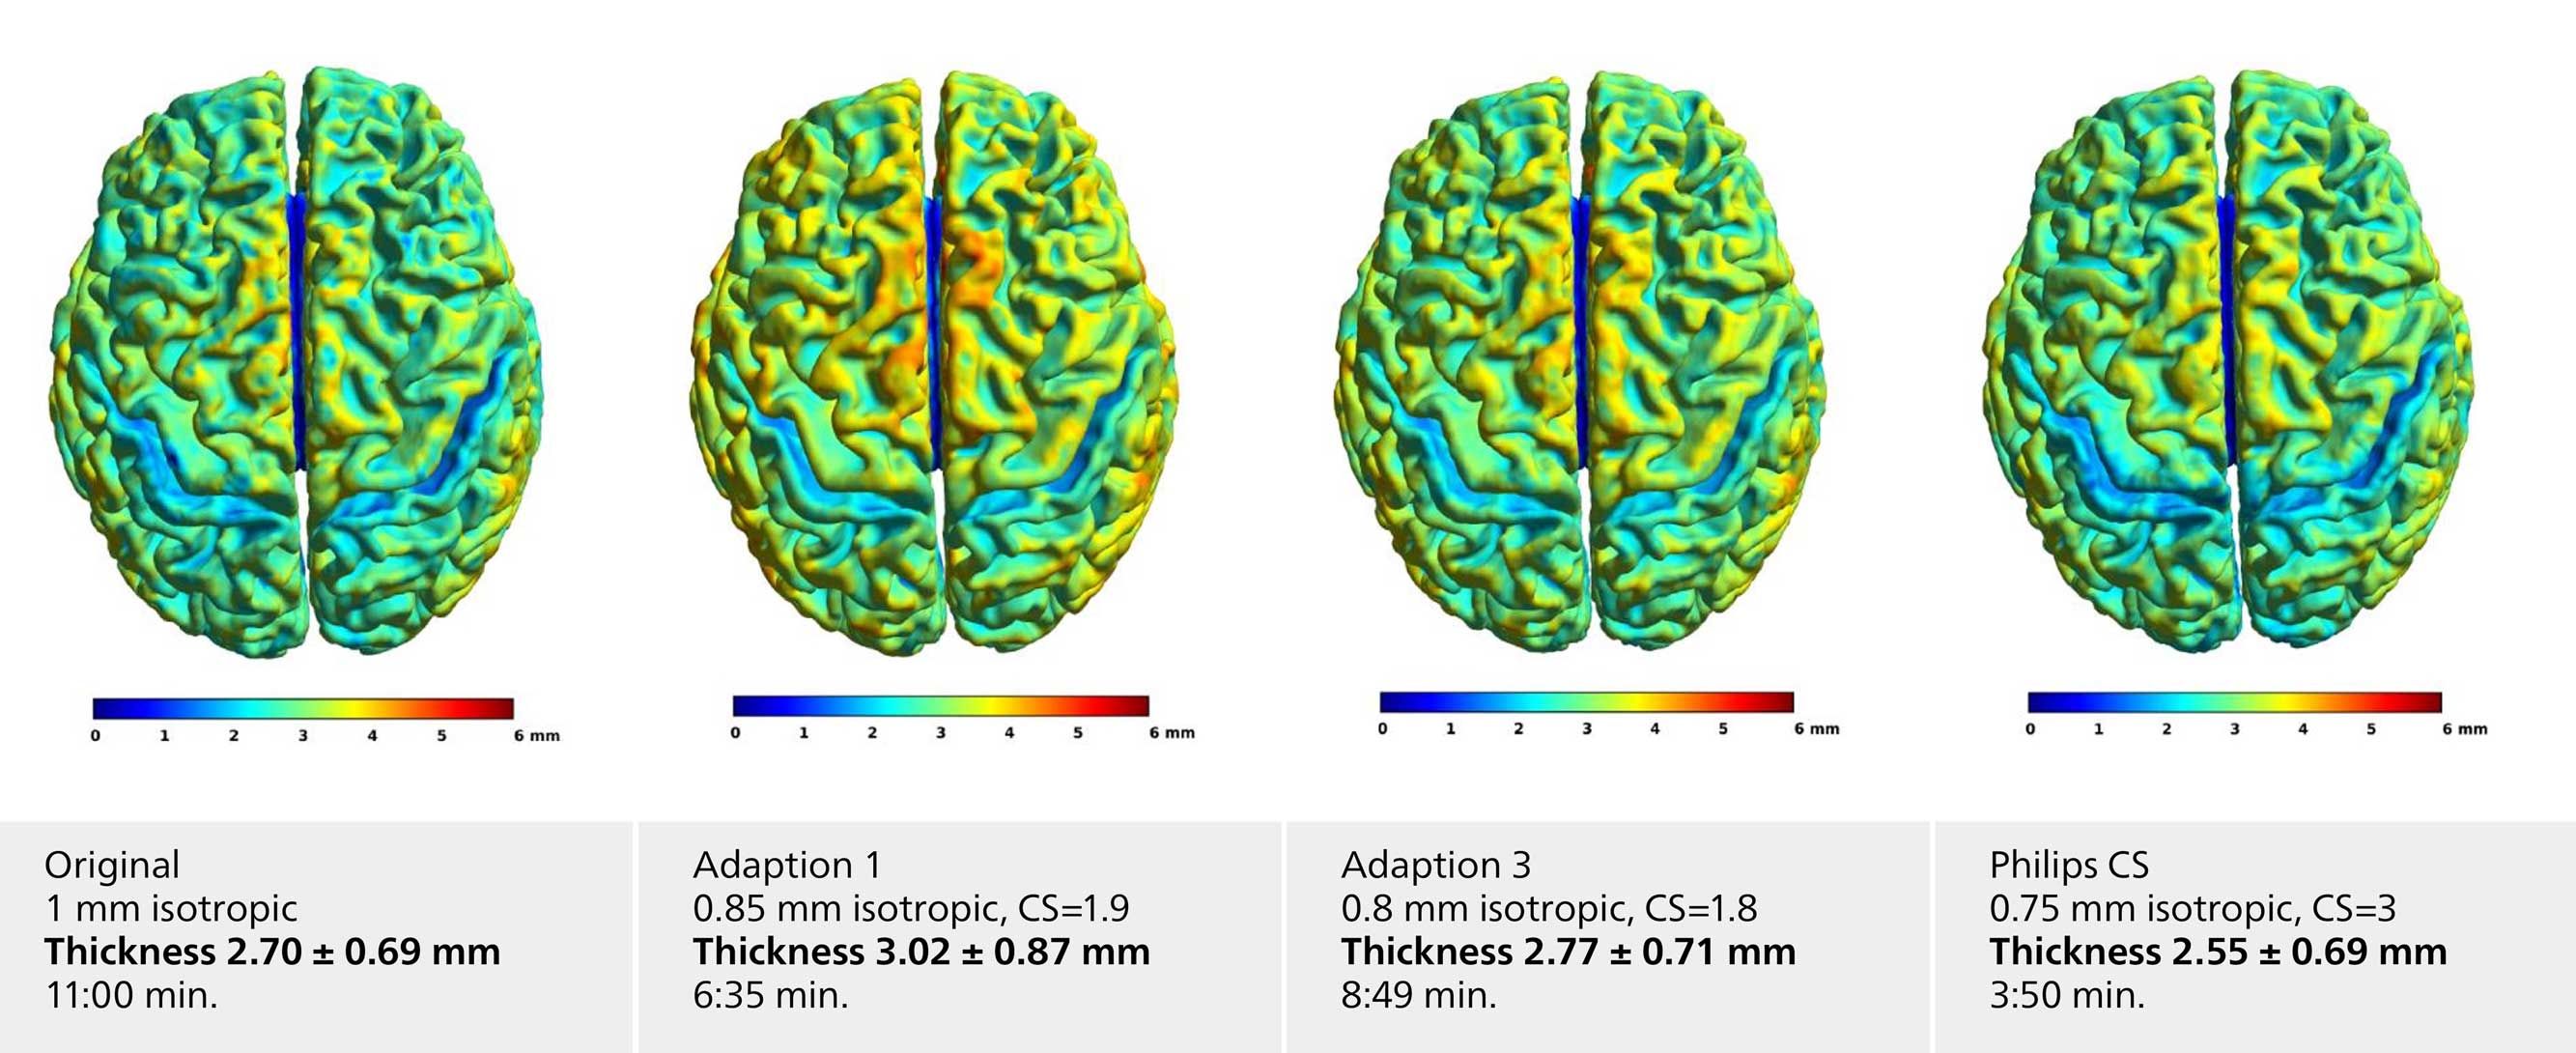

Voxel based morphometry

The neuroscience team compared their standard T1 brain morphometry sequence with alternate protocols facilitating Compressed SENSE. Selected examples shown here include adaption 1 with moderate CS=1.9, higher voxel resolution (0.85 mm), adaption 3 with CS=1.8 and 0.8 mm isotropic voxel size and the Philips protocol database default with CS=3.0 and 0.75 mm isotropic voxel size. All protocols resulted in comparable cortical thickness results with a slight decrease for higher CS-factors.

Voxel based morphometry

The neuroscience team compared their standard T1 brain morphometry sequence with alternate protocols facilitating Compressed SENSE. Selected examples shown here include adaption 1 with moderate CS=1.9, higher voxel resolution (0.85 mm), adaption 3 with CS=1.8 and 0.8 mm isotropic voxel size and the Philips protocol database default with CS=3.0 and 0.75 mm isotropic voxel size. All protocols resulted in comparable cortical thickness results with a slight decrease for higher CS-factors.